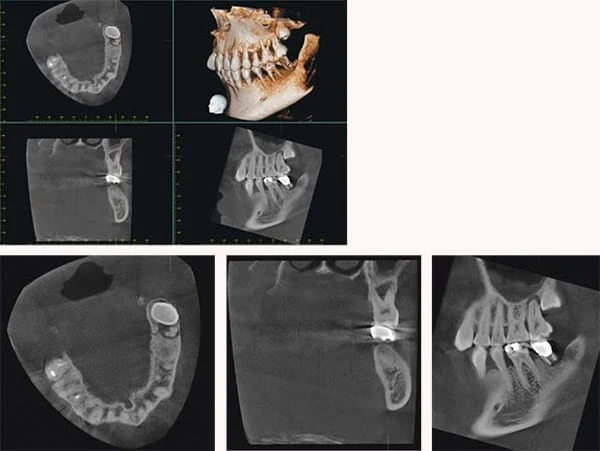

Phim mặt nhai hiển thị một vùng tương đối lớn của cung răng. Nó có thể bao gồm khẩu cái hoặc sàn miệng và một phần cấu trúc vùng tiếp giáp. Phim mặt nhai cũng hữu ích khi bệnh nhân không thể há miệng đủ rộng để chụp phim gốc răng hoặc những lý do nào đó mà không đặt receptor vùng chóp răng được. Phim mặt nhai có thể sử dụng cùng với phim quanh chóp để xác định xem vị trí của cấu trúc hoặc tổn thương theo ba chiều không gian. Thông thường, phim mặt nhai đặc biệt hữu ích trong những trường hợp sau:

– Để xác định chính xác vị trí chân răng và thành phần phụ, răng chưa mọc hoặc răng ngầm (kỹ thuật này đặc biệt hữu ích với răng cối lớn hoặc răng nanh mọc ngầm)

– Để xác định các vật thể lạ trong xương hàm và sỏi trong ống tuyến nước bọt dưới hàm và dưới lưỡi.

– Để xác định và đánh giá sự toàn vẹn của bờ trước, bờ giữa và bờ bên của xoang hàm trên.

– Để hỗ trợ việc kiểm tra trên bệnh nhân bị bệnh cứng khớp, chỉ có thể há miệng một vài milimet nên không thể chụp phim trong miệng được hoặc có thể chụp nhưng gây đau đớn cho bệnh nhân.

– Nhằm có được những thông tin về vị trí, tính chất, mức độ và sự thay đổi vị trí của đường gãy xương hàm trên và hàm dưới.

– Nhằm xác định xem mức độ lan rộng của các bệnh lý như nang, viêm tuỷ xương, bệnh lý ác tính… và phát hiện bệnh lý ở vùng khẩu cái hoặc sàn miệng.